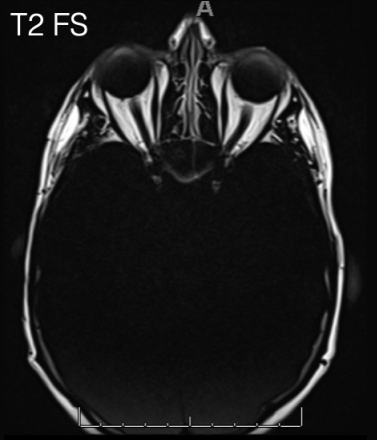

aliasing

also called Moire fringe artifact, commonly seen in GRE sequences and is a result of alternating constructive and destructive interference

Moire fringe artifact is commonly associated with what sequence?

GRE